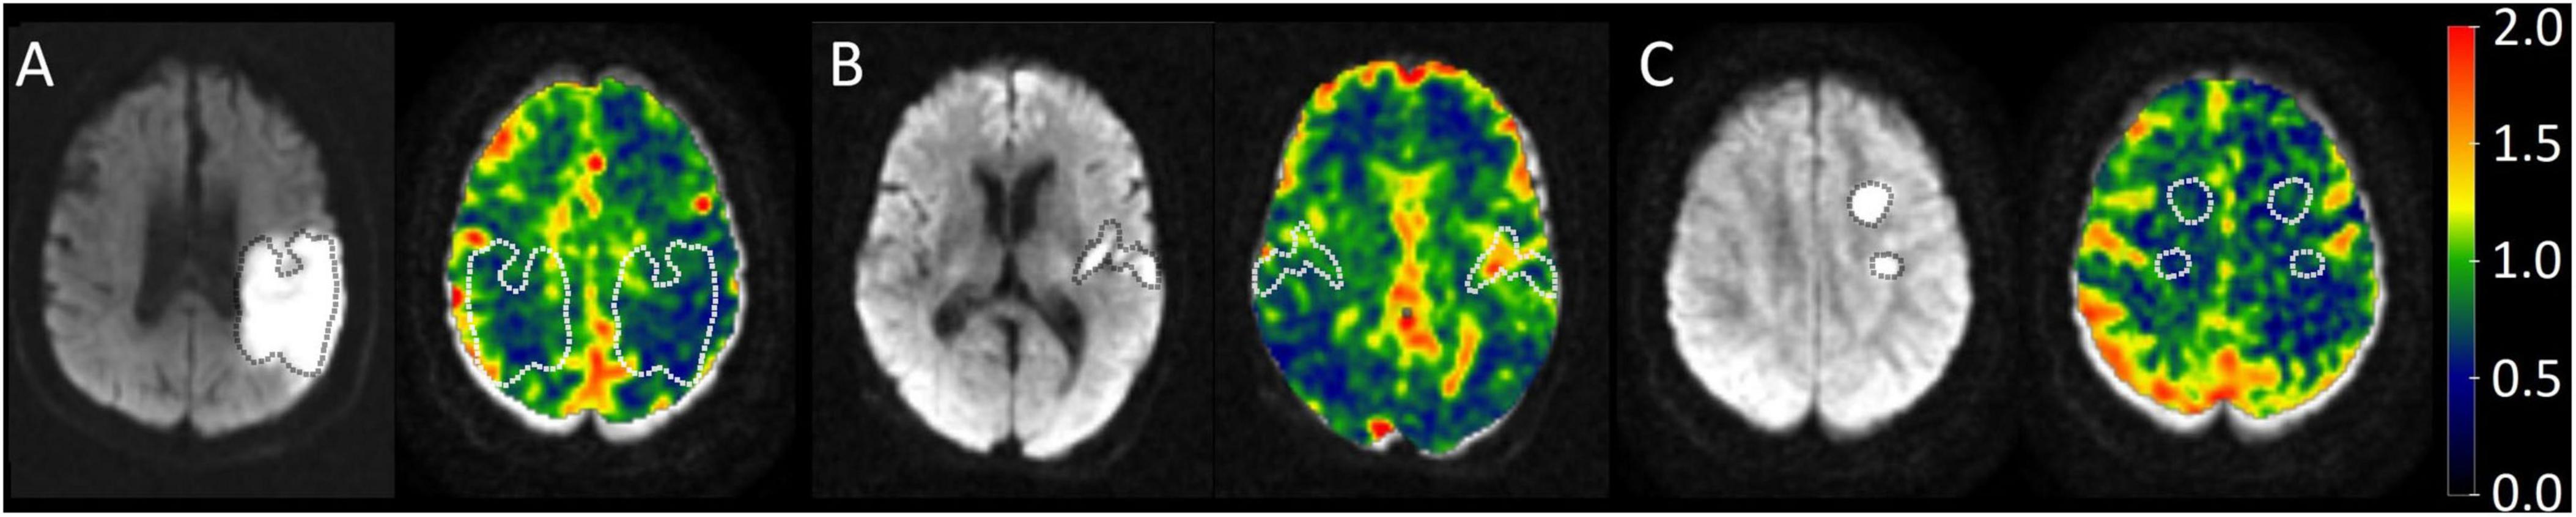

Two patterns were observed in the analysis of differences in ischemic and contralateral CVR values. Some patients displayed decreased reactivity in the contralateral hemisphere compared to the ischemic one, while others exhibited increased values, as illustrated in Figure 3. This possibility has been observed in stenosis patients (26), where some individuals may respond with increased or decreased activity in both severe and mild stenosis, regardless of the condition. This suggests a possible way to understand how the brain reacts to ischemic injury, acting as a measure of dynamic compensatory mechanisms. Figure 4 displays the average CVR when divided by anatomical location, inflammation, and outcome. In the ischemic hemisphere, CVR was notably lower in cortical regions than in subcortical areas (p = 0.01). A similar, though not statistically significant, trend appeared in the contralateral hemisphere (p = 0.06). Inflammatory status also seemed to affect CVR responses; participants with lower levels of systemic inflammation tended to have higher CVR values in the ischemic hemisphere, indicating a more preserved reactive vascular response under low inflammatory conditions. However, no consistent trend was observed in the contralateral hemisphere with inflammation. Although these findings did not reach statistical significance, they hint at a subtle influence of inflammation on acute vascular reactivity, particularly in ischemic regions. Regarding the clinical outcome, patients with poor functional recovery at 6 months demonstrated significantly higher CVR values in the contralateral hemisphere during the acute phase than those with favorable outcomes (1.12 ± 0.20 vs. 0.85 ± 0.11, p = 0.014). These findings emphasize the potential of CVR as a dynamic, non-invasive indicator of cerebrovascular adaptation and contralateral compensation, consistent with previous observations in chronic cerebrovascular conditions (26, 43). In acute stroke, early CVR evaluation could provide prognostic insights into the brain’s ability to adapt to localized ischemia and overall systemic vascular vulnerability.

FIGURE 3

MRI images showing brain scans in three panels labeled A, B, and C. Each panel contains two brain scans: one in grayscale and the other in color. The colored scans use a scale from 0.0 (purple) to 2.0 (red) to indicate different activity levels. White and dotted outlines highlight specific brain regions in each panel, with distinct intensities and patterns visible.

Figure 3. The diffusion-weighted images (DWI) on the left of each panel serve as a guide to identify the ischemic region, which is delineated with a dotted line. On the CVR maps, both the ischemic and contralateral regions are outlined to allow comparison. The color bar indicates lower CVR values in blue and higher values in red. (A) Patient 23 demonstrated decreased CVR. (B) Patient 11 showed increased CVR. (C) Patient 2 showed no significant differences in ROI CVR. Cerebro reactivity maps in three different subjects.